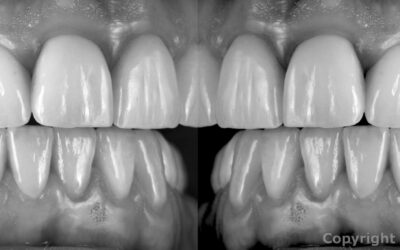

Restauro in Ceramica Integrale